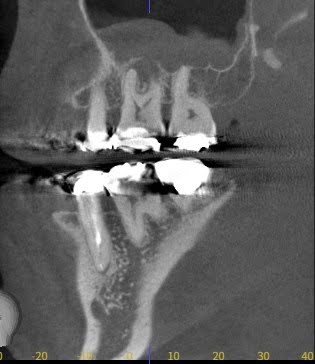

症例写真について

では、赤坂さくら歯科クリニックでの写真を見てみましょう。

以下の写真で治療前の写真ですが、上顎の6番の大きな根尖病変が上顎洞にまで波及しています。

上顎洞の白い不透過像(白く曇った像)も大きく見えています。

そして、治療後3ヶ月、根尖病変がなくなり、根尖の骨が治癒してきています。

上顎洞の白い曇った像も小さくなってきています。